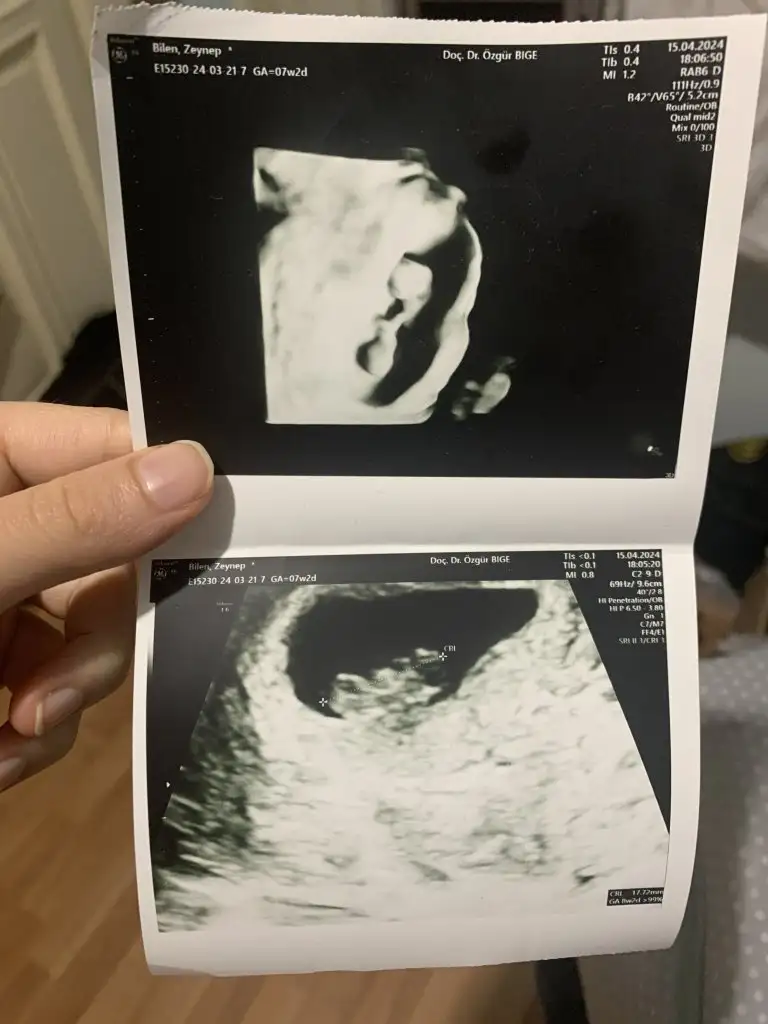

Kızlar sizce cinsiyet ne nuba göre herkez kız diyor kız olsa renkli ultrasonda bu kadar belirgin çıkıntı olurmu

Fotoya tekrar baktım bence kız bu erkek olması için çizginin yatay değil dik olmasi lazım seni ki yatay gidiyor benim kide öyleydi doktor kız dedi inşallah gönlünden geçen olur

Çizgiden kastınız nedir acaba onu anlayamadım, kendime de bakacağım da :)